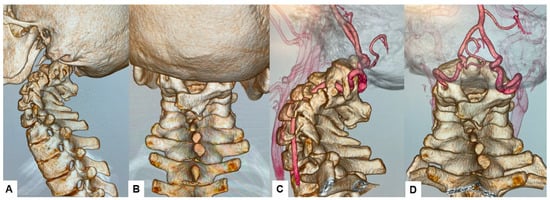

2.3. Preoperative Imaging

2.4. Surgery